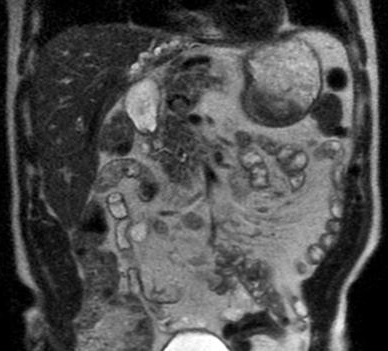

Aspect de fibrose

stenosant multifocale avec dilatation

segmentaire systematise de voie biliaire

intrahepatique du foie droit ( cholangite

sclerosant primitive ) . Image radiologique

IRM en coupe coronal , pondere sur T2 |